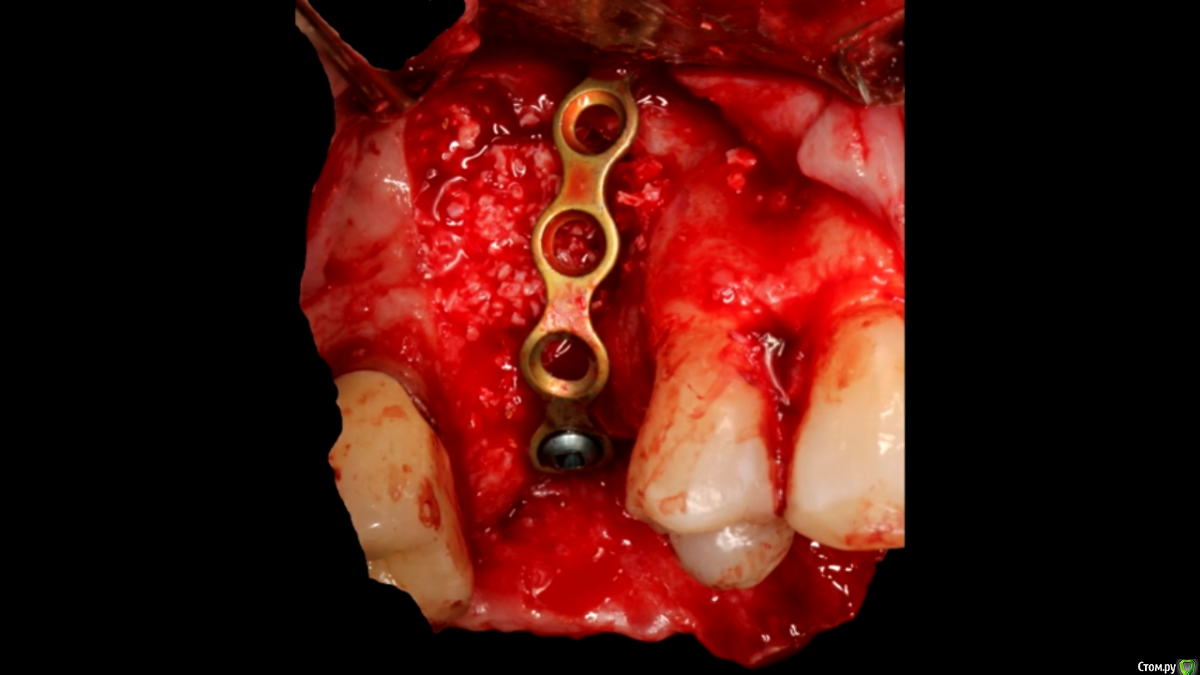

Доктор Добрых Дел Опубликовано 25 мая, 2017 Поделиться Опубликовано 25 мая, 2017 То, что пластина это каркас понятно. По крайней мере с этого ракурса я не увидел, что пластина восполняет какой-либо вертикальный дефект. Кажется, что она просто перекрывает окно ( максимум отстоит от гребня вестибулярно) Возможно ракурс неудачный Ссылка на комментарий

Nazim_NV86 Опубликовано 28 мая, 2017 Поделиться Опубликовано 28 мая, 2017 Зачем тратиться на птфе или титановые сетки или даже обычные коллагеновые мембраны именно в этом случае, если недорогая пластина всё сделает. Я понял это так. Ссылка на комментарий

Bier Опубликовано 29 мая, 2017 Автор Поделиться Опубликовано 29 мая, 2017 Зачем тратиться на птфе или титановые сетки или даже обычные коллагеновые мембраны именно в этом случае, если недорогая пластина всё сделает. Я понял это так.мембрана тут была использована. Барьерные функции нужны. Ссылка на комментарий